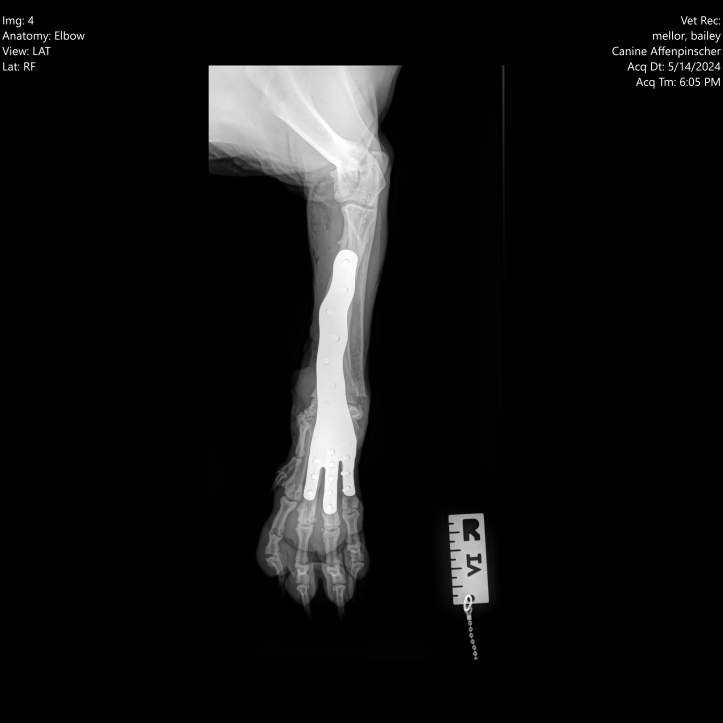

In 2023, Bailey was admitted to Dovecote Veterinary Hospital, where Orthopaedic Specialist James Pratt performed a combined angle correction and partial carpal arthrodesis (PCA) to address the deformity and the resulting arthritis. This advanced surgical procedure involved the use of cutting-edge technology to ensure precision and effectiveness.

James, along with a highly trained surgical team, employed 3D-printed guides made by Bill Oxley at Vet3D to make precise cuts in the correct direction. These guides were tailored specifically for Bailey's unique anatomical structure, ensuring optimal accuracy. Following the bone cuts, a custom 3D-printed plate was used to align the bones correctly while the carpal joints fused. This approach not only facilitated the proper alignment of Bailey's carpus, but also promoted successful joint fusion, ultimately relieving the pain associated with osteoarthritis.